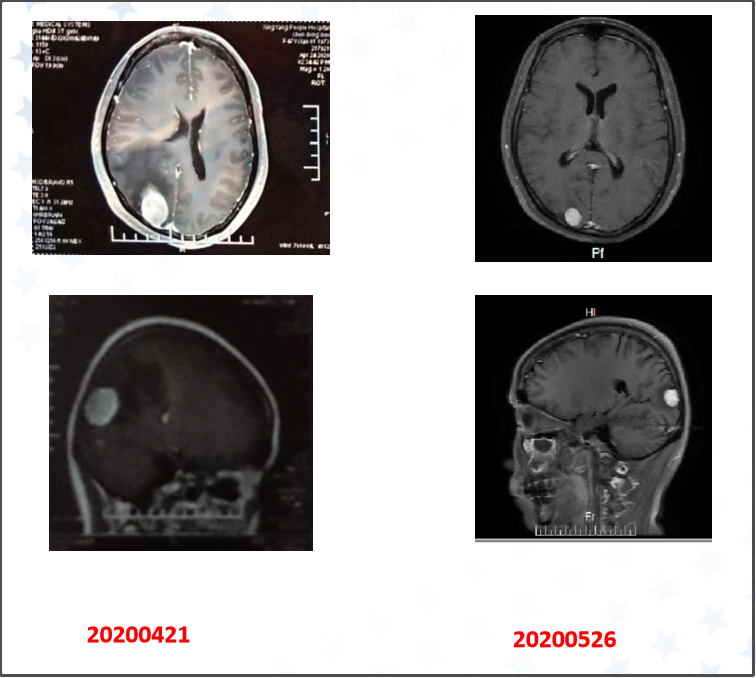

第二个病例为一位晚期患者,49岁女性,2015年发病,2020年出现枕叶转移,表现为头晕、头痛、恶心,经达拉非尼联合曲美替尼双靶治疗3天后头痛减轻,1周后症状完全缓解,1个月后复查病灶明显缩小。以上2例患者都是达拉非尼联合曲美替尼双靶方案刚在中国上市时就采用该方案进行治疗的患者,疗效非常好,这为我们后续采用该方案治疗树立了信心。